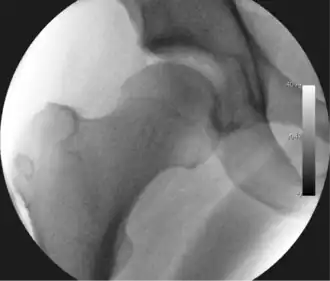

Figure 3. Fluoroscopic picture showing a mild amount of distraction of the hip before insertion of any instruments

The procedure is performed with the patient asleep (general anaesthetic) or under spinal anaesthesia. There are two widely used methods, one with the patient on their back (supine) and the other on their side (lateral decubitus). Which is used is down to the surgeon's preference. To gain access to the central compartment of the hip joint (between the ball and socket), traction is applied to the affected leg after placing the foot into a special boot. (See fig. 2) There is specifically designed equipment for this, although some surgeons use a 'traction table', initially designed to help in the operative fixation of broken thigh and lower leg bones. The amount of traction (or pull) needed is assessed with the help of fluoroscopy (low-dose portable x-ray). (See fig. 3) It is usually not possible to distract the ball from the socket with traction alone by more than a few millimetres. Once the surgeon is happy that they will be able to gain access to the hip joint (i.e. the ball will distract from the socket by a small amount), the patient is then painted with antiseptic and the surgical drapes applied.

The next step is to insert a fine needle under x-ray guidance into the hip joint. This breaks the 'suction seal' of the joint and allows further distraction if necessary (see fig 4). The surgeon wishes to see the ball move out the socket by approximately 1 cm, so that access to the hip joint can be achieved with minimal risk of damage to the joint surfaces. Most surgeons will inject fluid into the joint at this stage, again to ensure that there is enough space between the ball and socket for safe instrument access. This needle is then removed. The next step is placement of the 'portals', or the small holes made to pass instruments into the joint. This is achieved by again passing a fresh hollow needle into the joint under x-ray control, usually in a slightly different position. The reason for this is so the surgeon can ensure that the needle, and subsequent cannulae do not penetrate and damage the acetabular labrum or cartilage joint surfaces (see fig. 5). Again, surgeons will have their own preferences as to their preferred placement. Through this hollow needle, a long thin flexible guide wire is passed into the joint, and the needle is removed over it, leaving the guide wire in situ. A small cut in the skin is made around the wire, to allow for larger cannulae to be placed over the wire through the portal. The wire therefore guides the larger cannulae into the joint. The most common external diameters of cannulae used are between 4.5 and 5.5 mm. Once the surgeon is satisfied that the cannula is in the correct position, by a combination of feel and x-ray guidance, the guide wire can be withdrawn. Once the first portal is correctly placed, any further portals may be created once the camera is in position, to ensure that they are placed with minimal risk to the joint surfaces. This process can be repeated to gain as many points of entry to the hip joint as the surgeon requires, normally between two and four. Certain of these entry points will be used for the viewing arthroscope and others for operating instruments.

Standard arthroscopic treatment of symptomatic cam FAI involves debridement (resection) or repair of any labral [10] and chondral injuries [11] in the central compartment of the hip, and subsequent reshaping of the head-neck junction of the upper femur (osteochondroplasty) in the peripheral compartment [12][13] using high-speed motorised burrs that are similar in design to a dentist's drill (see fig. 9).